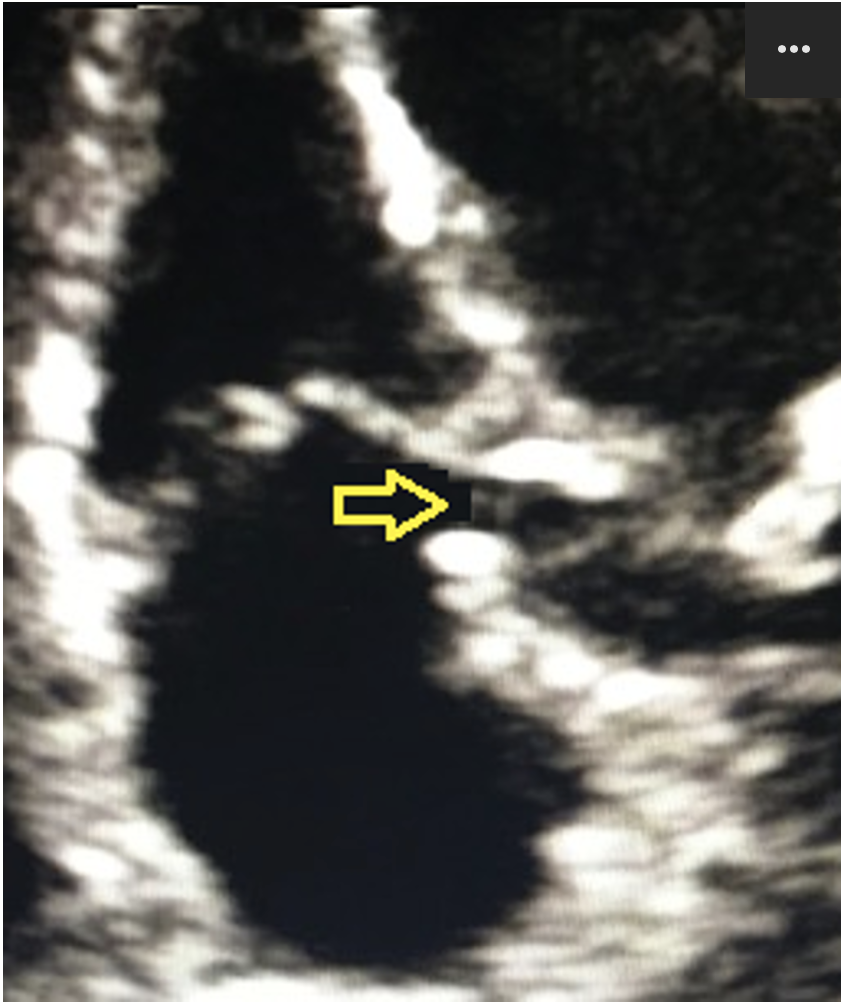

19

Q

What view is being demonstrated?

a) Apical 2

b) Apical 4

c) Apical 3

d) Apical 5

A